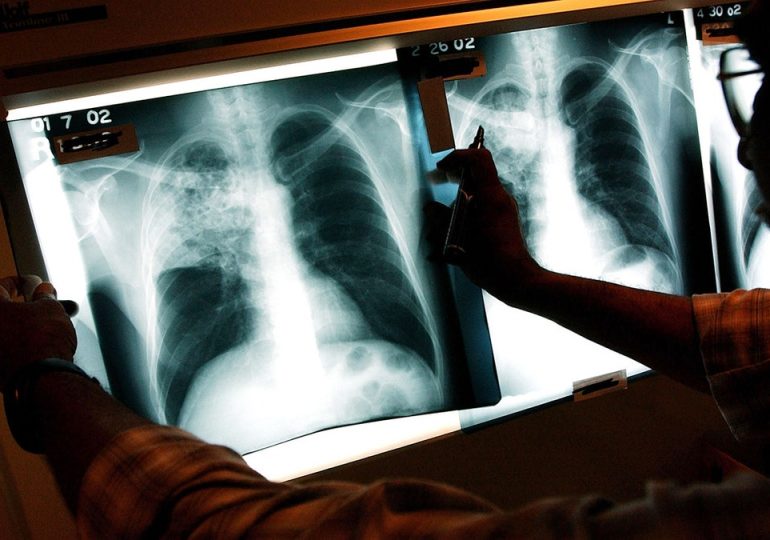

Three active tuberculosis cases reported in Maine as deadly disease continues to tick up across country

NEWYou can now listen to Fox News articles! There are three active cases of tuberculosis in Maine as of this week as TB continues to increase across the country, the…